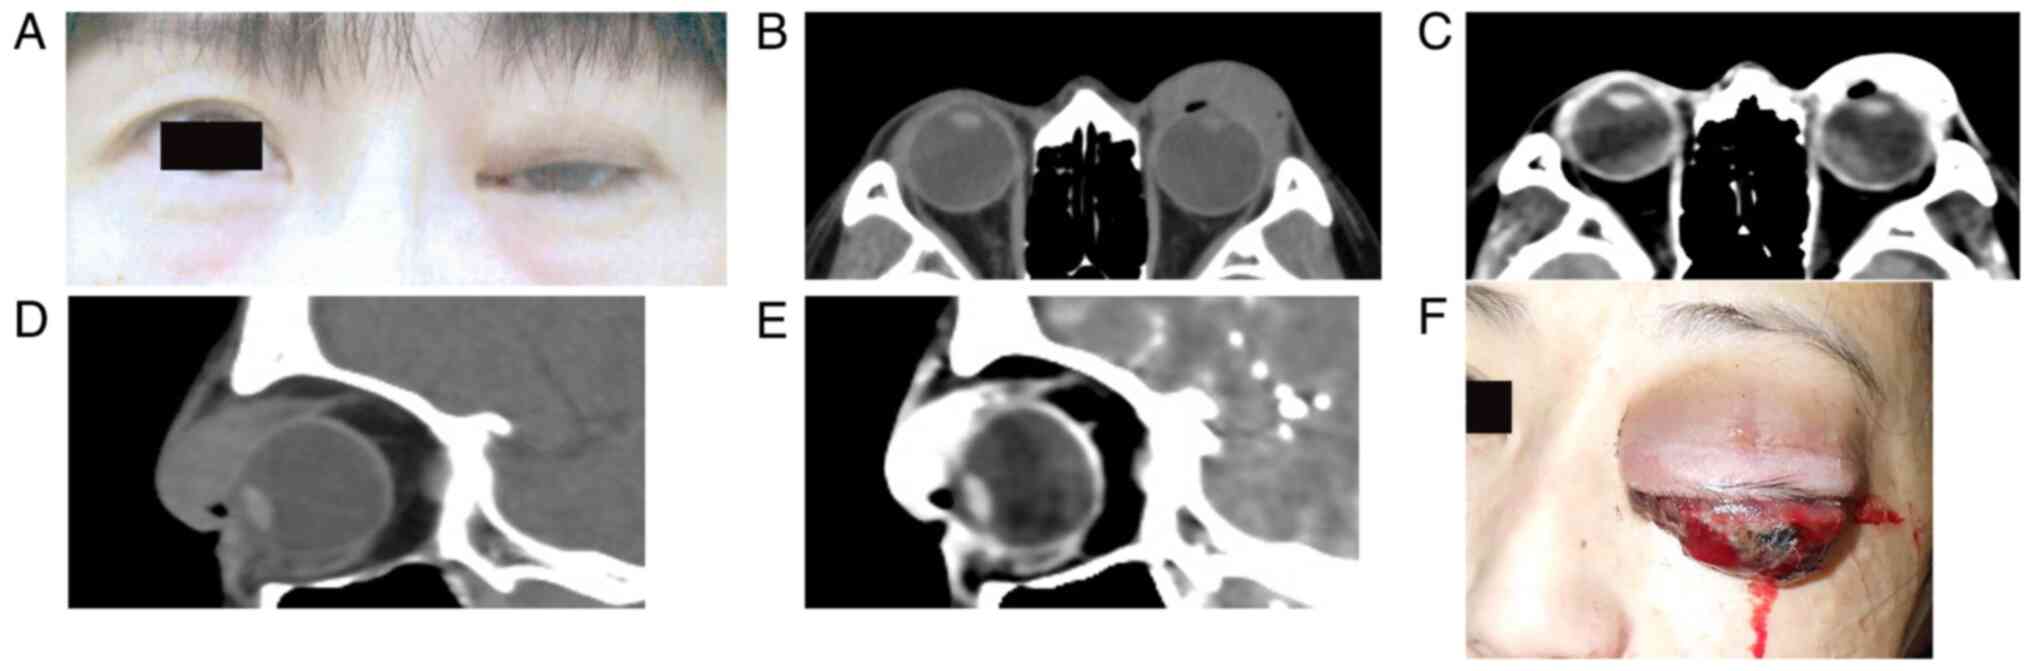

A 44-year-old Japanese woman presented at her local clinic with a left upper eyelid nodule measuring about 2 fingers broad in February 2023. The patient was healthy without any remarkable medical history. The ophthalmologist at a nearby clinic attempted to aspirate the tumor, but only some blood was collected, and thus, the patient was observed without any biopsy of the lesion. The nodule gradually enlarged and grew away from the eyelid conjunctiva over 2 months, so the patient was referred for plastic surgery at a nearby hospital in April 2023. There was a pigmented conjunctival mass in the upper palpebral conjunctiva (Fig. 1A). Computed tomography (CT) showed a large eyelid tumor invading the anterior orbit (Fig. 1B and D). Enhanced CT demonstrated marked enhancement in the left eyelid in the artery phase, indicating hemangioma (Fig. 1C and E), while there were no lesions in the deep orbit. Therefore, the plastic surgeon followed up the patient based on the radiological report. Whole-body CT with enhancements (data not shown) revealed no enhancement in the body except for the left periocular region. The conjunctival mass further enlarged, where bleeding was noted in May 2023. The surgeon conducted a transcutaneous biopsy of the eyelid mass. In the following week, the patient accidentally suffered blunt trauma to her face and continuous bleeding from the tumor occurred. Doctors in the emergency room attempted hemostasis by diathermy and suture, but the bleeding could not be stopped. Although no pathological diagnosis had been made, the patient was referred to Hokkaido University Hospital (Sapporo, Japan) in June 2023. At this initial presentation, the left eyelid showed marked swelling with persistent bleeding (Fig. 1F). The eyelid had acquired a reddish coloration without any pain or tenderness. A large elastic, hard mass was palpable beneath the entire eyelid skin. The surface of the tumor was admixed with pigmentation and fresh bleeding, with reddish elevation. The visual acuity, intraocular pressure and fundus could not be fully examined because the mass lesion blocked the ocular tissues. The conjunctival mass was clinically diagnosed as giant conjunctival melanoma exclusively based on clinical findings of an elastic hard mass with pigmentation. The patient was taken to the operating room and emergent orbital exenteration was conducted about 2 h after arrival at our out-patient ward following the obtainment of informed consent. Just before the orbital exenteration, the patient's consciousness was clear, the heart rate was normal at 69/min, the body temperature was normal at 36.7˚C, blood pressure was normal (117/80 mmHg) and oxygen saturation was 98%, whereas a blood test revealed anemia, showing a low number of red blood cells (3.68x1012/l; reference value, 4.35-5.55x1012/l), hemoglobin (9.9 g/dl; reference value, 13.7-16.8 g/dl) and hematocrit (31.6%; reference value, 40.7-50.1%). After removal, the persistent bleeding resolved. The pathology report of biopsy tissue taken by the plastic surgeon indicated the presence of numerous atypical epithelioid cells with high cellularity. The nuclei were round with clear nucleoli. There were necrotic foci and pigmentation within the tumor tissues. The atypical cells were positive for melanocytic markers, human melanoma antigen (HMB45) (monoclonal; pre-diluted; cat. no. 413851; Nichirei Corp.) and Melan A (monoclonal; pre-diluted; cat. no. 413381; Nichirei Corp.), but negative for epithelial markers, AE1/AE3 (monoclonal; pre-diluted; cat. no. 760-2135; Roche Diagnostics) and cytokeratin (CAM5.2; monoclonal; pre-diluted; cat. no. 349205; BD Bioscience) and stromal and endothelial cell marker CD34 (monoclonal; pre-diluted; cat. no. 413111; Nichirei Corp.). Those findings allowed for a pathological diagnosis of malignant melanoma, which was conveyed to our hospital from the initial external hospital after the exenteration. H&E staining and immunohistochemistry was performed according to standard procedures.

Figure 1

(A) External ocular presentation: Left eyelid swelling can be noted. (B) Unenhanced and (C) enhanced CT of the eye region in April 2023 by horizontal section, showing an eyelid tumor with marked intensity on enhancement. (D) Unenhanced and (E) enhanced CT in April 2023 by sagittal section, showing a mass lesion along with the superior rectus muscle and tumor invasion to the anterior orbit, respectively. (F) Just before exenteration, the left eyelid showed marked swelling with relentless bleeding. CT, computed tomography.